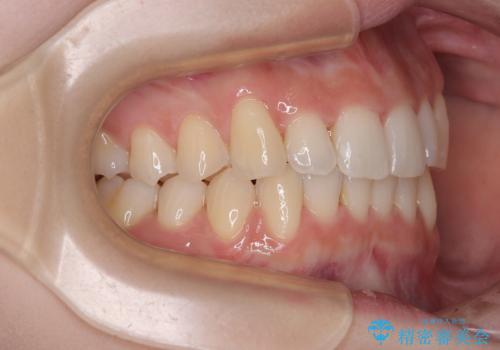

前歯が隠れるほどのデコボコをインビザライン矯正できれいに整える

- 前歯のデコボコを気にして来院された患者様です。

全体的にデコボコが多く、特に下の前歯は隠れてしまうほどの状態でした。

左右ともに奥歯の咬み合わせが理想的な位置にあったこともあり、患者様のご希望通り、インビザラインにて矯正治療を行うこととしました。